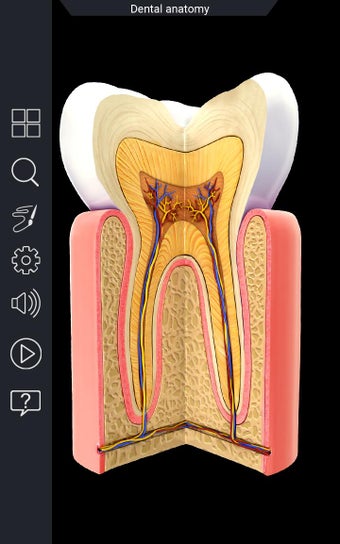

Una aplicación gratuita para Android, creada por Visual 3D Science.

La anatomía humana es una aplicación educativa médica que te permite explorar el cuerpo humano desde todos los ángulos. Ofrece una mirada detallada a la anatomía de los diferentes sistemas, así como a los órganos y sus funciones. Es una referencia perfecta para estudiantes y profesores de medicina.

Puedes seleccionar cada parte del cuerpo por separado para ver su nombre o leer información relacionada. Puedes ocultar y mostrar cada parte del cuerpo, así como rotar 360° alrededor de un modelo 3D altamente realista. Puedes dibujar en la pantalla o compartir capturas de pantalla con tus amigos. Puedes encontrar la definición de cada parte del cuerpo y su anatomía.